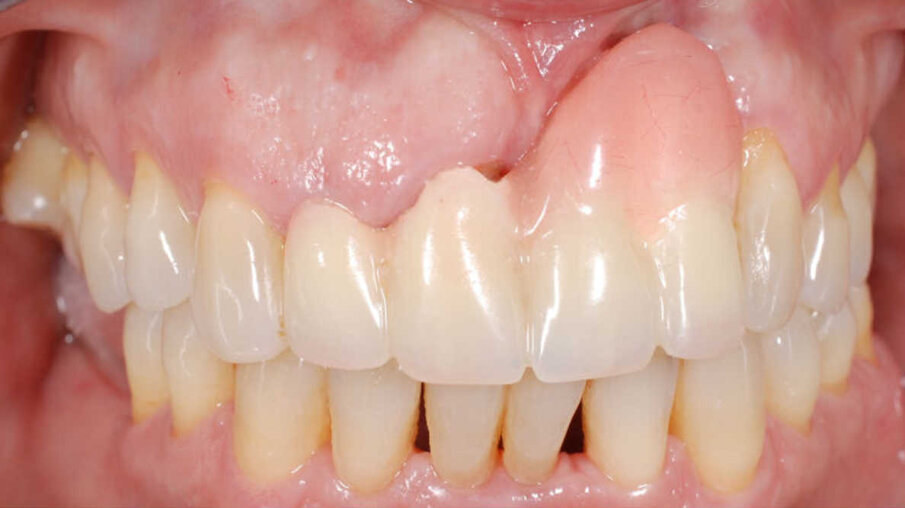

Dans cet article, nous présentons un cas clinique qui montre comment une mauvaise mise en place d'un implant peut rendre impossible la réhabilitation prothétique, ce qui nécessite une nouvelle planification chirurgicale et de réhabilitation pour obtenir l'esthétique souhaitée. Le patient se présente à notre observation avec une réhabilitation prothétique incongrue, avec bride en résine, support dentaire et implantaire, avec la présence d'un implant en position 2.1 vestibulaire et avec l'émergence dans le fornix, dans la mucosa alvéolaire. L'évaluation de la tomodensitométrie montre la position incorrecte de l'implant et la perte constante dans le sens transversal de la structure osseuse (Figs. 1, 2). Par conséquent, le plan de traitement suivant a été choisi : retrait de l'implant et préparation prothétique de l'élément 2.3, fabrication d'un premier support dentaire temporaire pour guider la cicatrisation des tissus (Figs. 3-7). Après 4 mois, une greffe d'épithélium conjonctif libre est réalisée avec ablation du palais pour compenser l'espace transversal des tissus mous, puis le provisoire est remodelé afin de faciliter la cicatrisation des tissus (Figures 8-11). Après 9 mois de maturation des tissus, la finalisation prothétique fixe avec support dentaire est réalisée (Figs. 12-14).

Quelle qu'en soit la cause, lorsqu'un implant n'est pas bien placé, la réhabilitation prothétique peut ne pas être adéquate sur les plans mécanique, fonctionnel et esthétique. Dans le cas présenté ici, le retrait de l'implant et une nouvelle planification chirurgicale et prothétique étaient nécessaires. Malgré les limites esthétiques de la réhabilitation prothétique initiale, considérant qu'aucune greffe osseuse n'a été réalisée sans réinsertion de l'implant, mais avec une bonne gestion des tissus mous, un résultat esthétique valide et prévisible a été obtenu avec le temps.